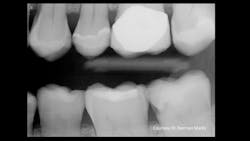

Figure 1: Current-generation bitewing digital dental radiograph shows some dental caries activity.

Recently, one of our practicing dentist team members who donates significant time to Clinicians Report Foundation and Practical Clinical Courses sent me a clinical example that frustrated both of us (figures 1 and 2). As you observe Figure 1, you will immediately see a lesion on the mandibular second molar and—perhaps—a small lesion on the maxillary first premolar. But do you see the lesion on the maxillary second molar? As you observe Figure 2, you are shocked to see the depth of the MO lesion that was not visible on the radiograph.